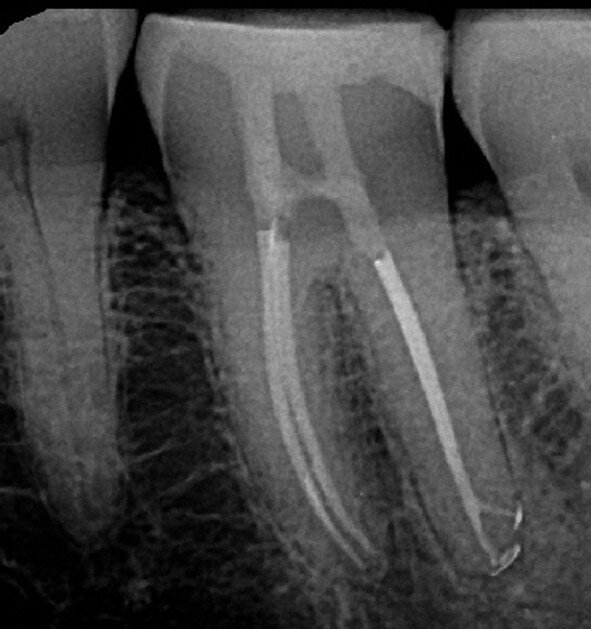

Figs. 12a–d : Depuis la gauche : Cas de l’auteur : dent

37 présentant une fracture radiculaire ; cette dent

montée dans un modèle en plâtre-pierre après extraction,

avec impression du guide de forage CTGEA

monté et du premier foret en place ; les deux

petits orifices d’accès préparés au moyen du guide

de forage ; et la radiographie postopératoire montrant

l’adaptation des cônes dans les canaux après leur négociation et leur mise en forme.